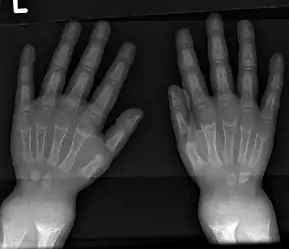

An X-ray or radiograph of an advanced sufferer from rickets tends to present in a classic way: the bowed legs (outward curve of long bone of the legs) and a deformed chest. Changes in the skull also occur causing a distinctive "square headed" appearance known as "caput quadratum".[14] These deformities persist into adult life if not treated. Long-term consequences include permanent curvatures or disfiguration of the long bones, and a curved back.[15]

- Radiography typically show widening of the zones of provisional calcification of the metaphyses secondary to unmineralized osteoid. Cupping, fraying, and splaying of metaphyses typically appears with growth and continued weight bearing.[39] These changes are seen predominantly at sites of rapid growth, including the proximal humerus, distal radius, distal femur and both the proximal and the distal tibia. Therefore, a skeletal survey for rickets can be accomplished with anteroposterior radiographs of the knees, wrists, and ankles.[39]